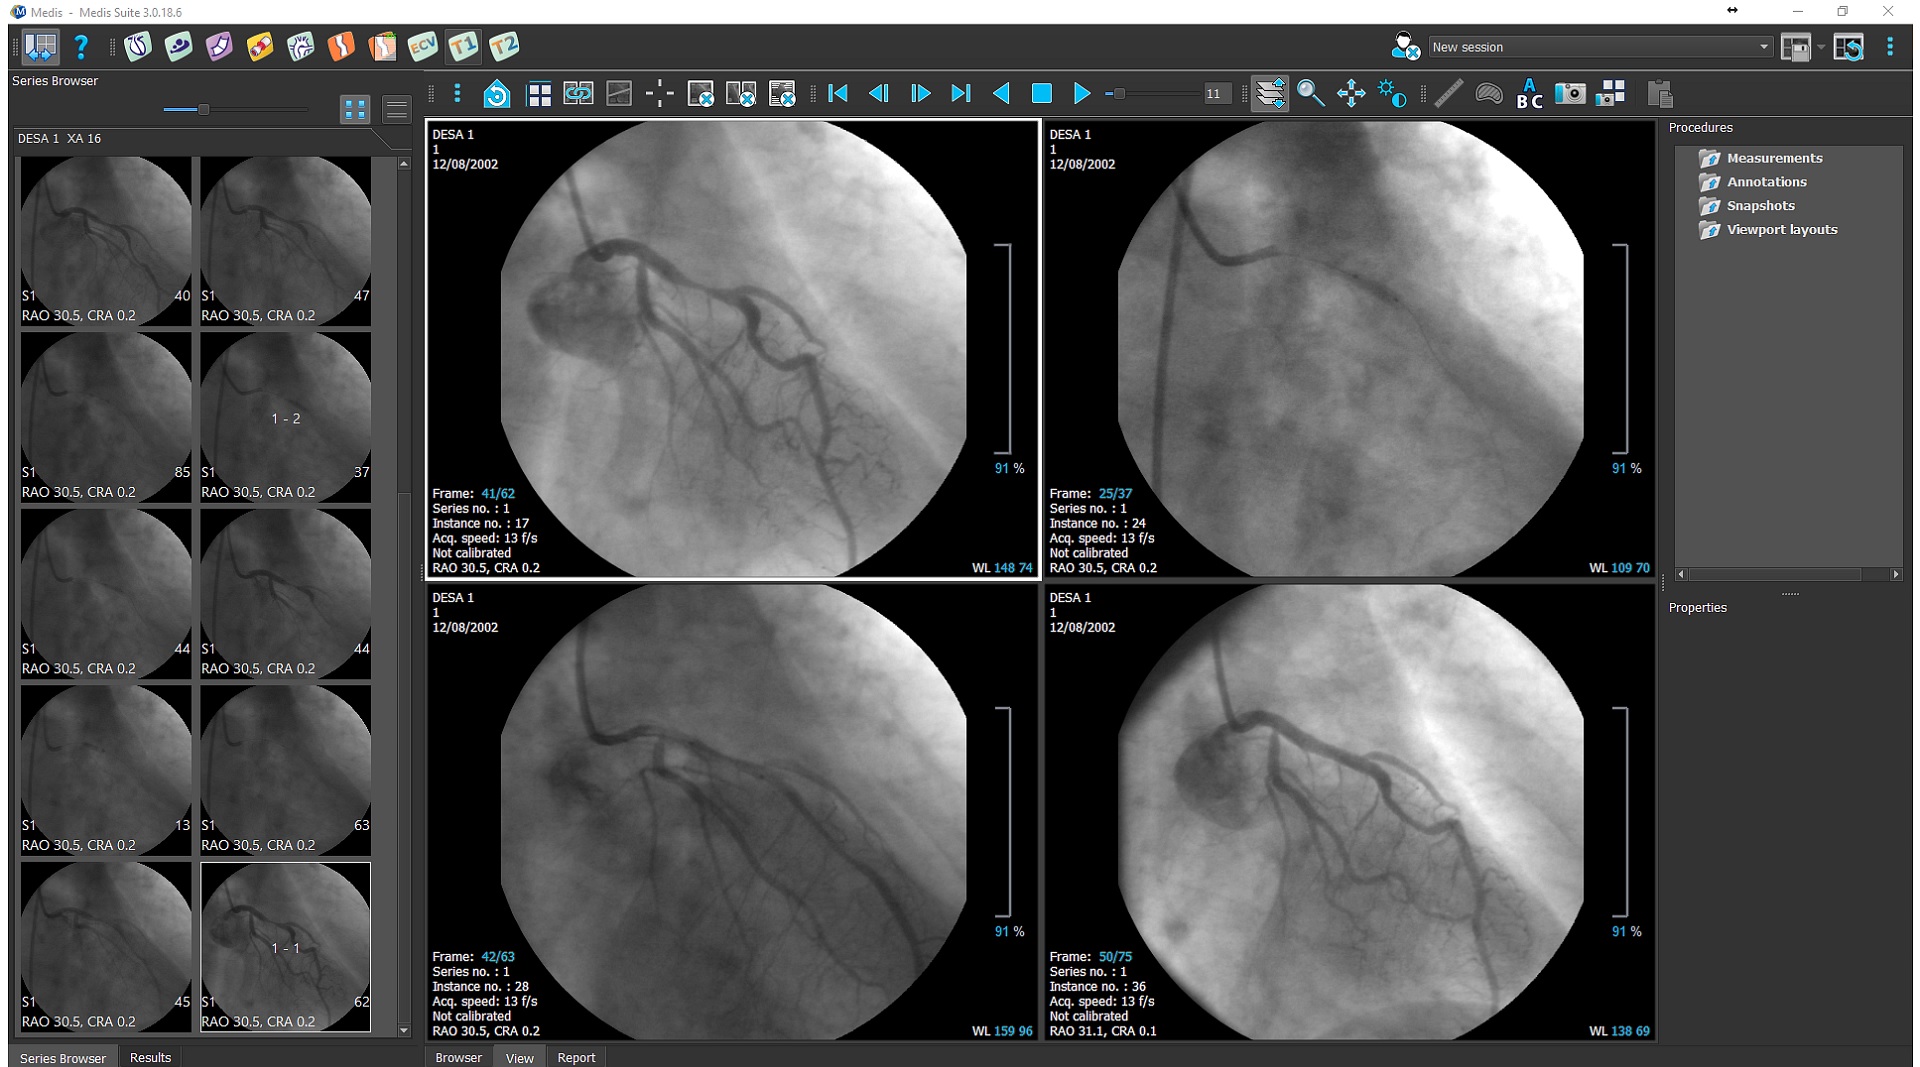

Vendor-independent post-processing solution for X-Ray angiography